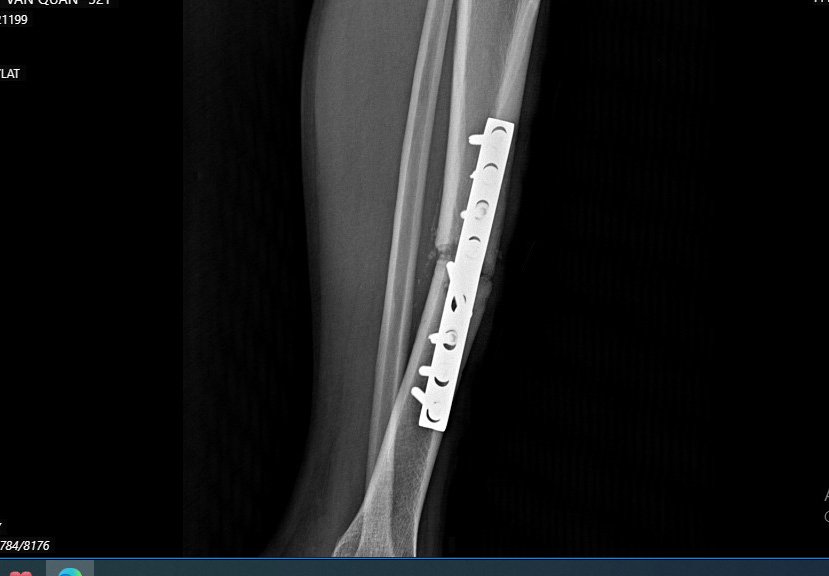

Hình ảnh xương chày 1/3 giữa di lệch hoàn toàn, khuyết xương mặt sau

Ekip phẫu thuật đã rạch da theo bờ trước xương chày phải, tách tổ chức dưới da qua các lớp cân cơ vào ổ gãy, thấy xương chày 1/3 giữa di lệch hoàn toàn, khuyết xương mặt sau. Các bác sỹ đã lấy xương xốp và vỏ xương đoạn gai chậu trước trên ghép vào mặt sau xương chày. Đồng thời, tiến hành làm sạch ổ gẫy và kết hợp xương bằng nẹp 8 lỗ 08 vít. Sau gần 2 giờ, ca phẫu thuật thành công. Hiện nay, bệnh nhân đang được điều trị tại khoa ngoại.

Chân bệnh nhân Q sau ca phẫu thuật